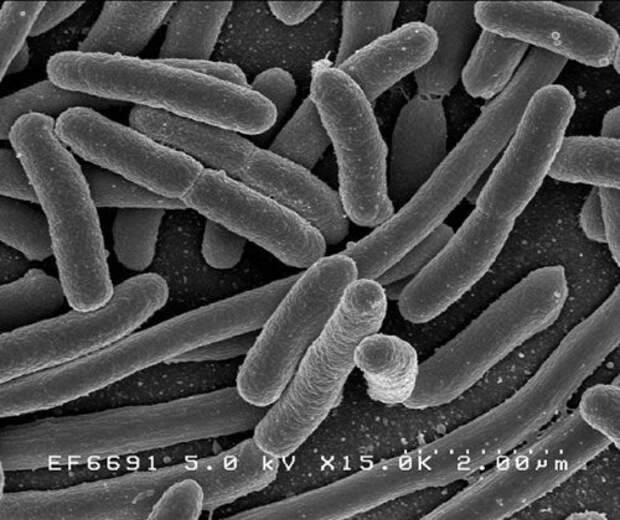

14. Возникновение пептических язв не связано со стрессом или неправильным питанием. Исследователи выяснили, что возбудителем этого недуга является бактерия под названием хеликобактер пилори (Helicobacter pylori).

Фото: Love Food Hate Waste NZ

5. Кишечник человека – это очень сложная экосистема, в которой обитает от 300 до 500 видов бактерий.

Фото: Wikipedia Commons.com

14. Возникновение пептических язв не связано со стрессом или неправильным питанием. Исследователи выяснили, что возбудителем этого недуга является бактерия под названием хеликобактер пилори (Helicobacter pylori).

Фото: Love Food Hate Waste NZ

5. Кишечник человека – это очень сложная экосистема, в которой обитает от 300 до 500 видов бактерий.

Фото: Wikipedia Commons.com